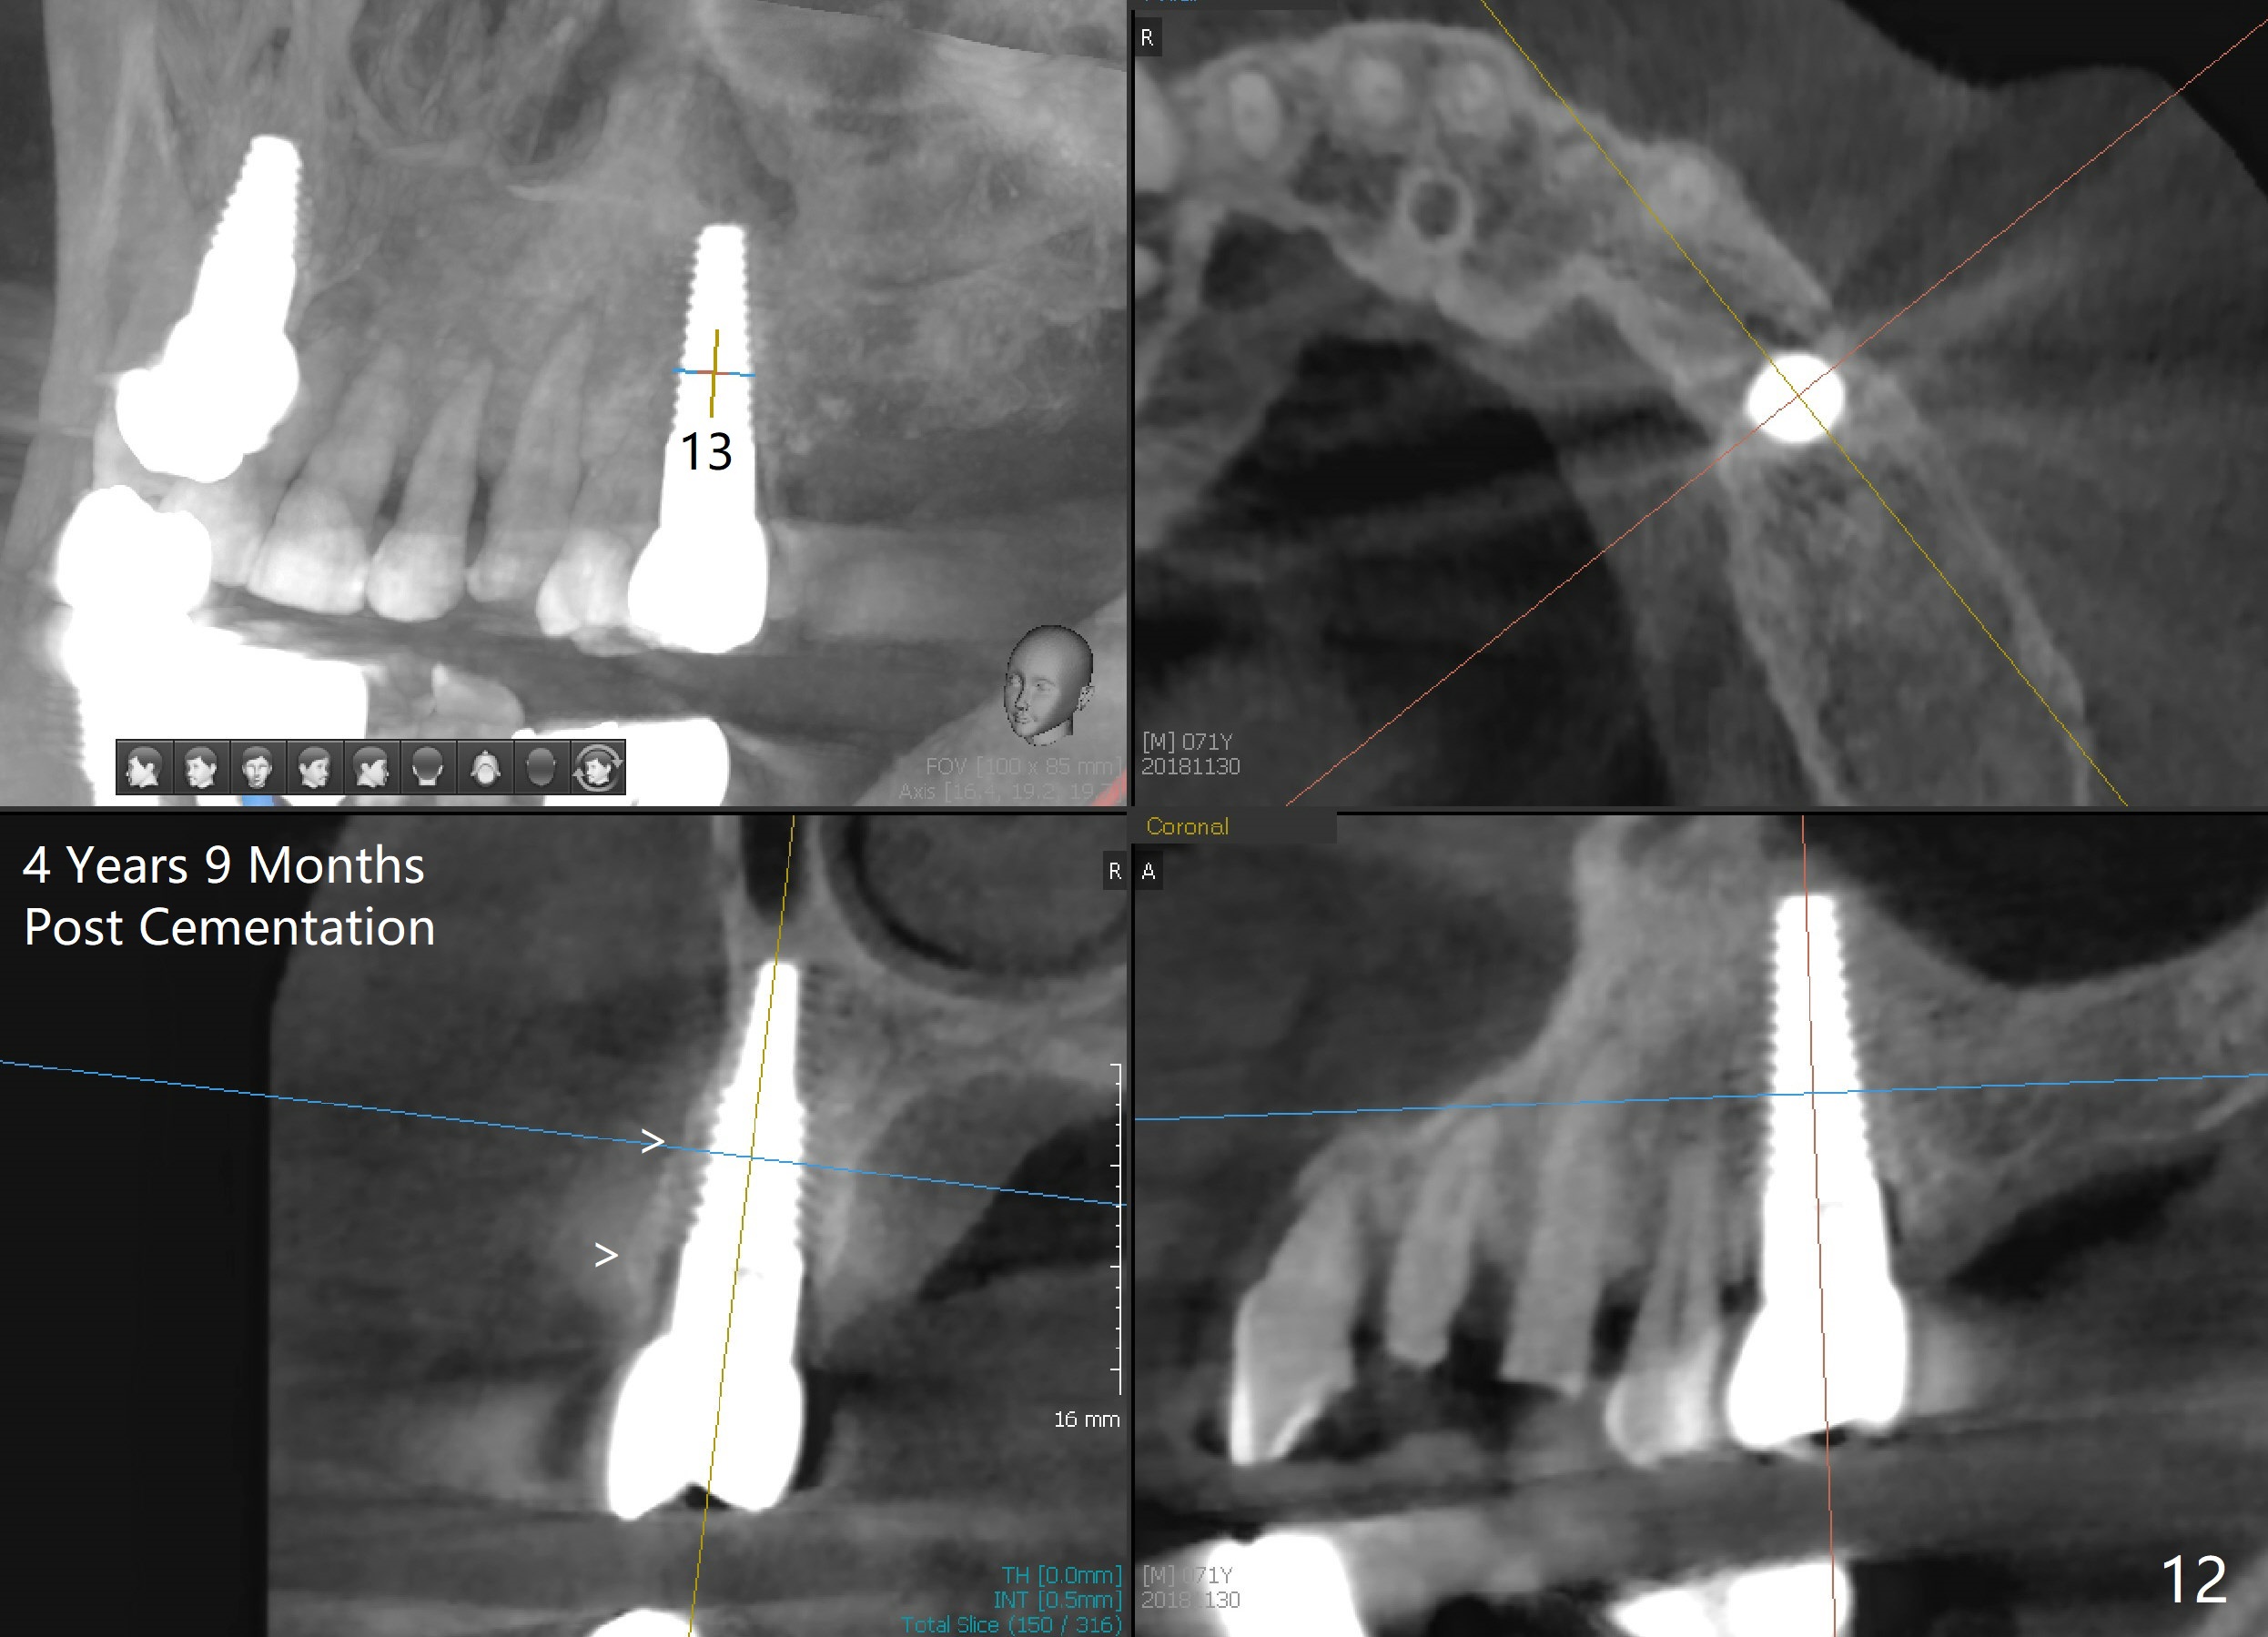

CT taken 4 years 9 months post cementation shows that the coronal portion of the buccal plate regenerates (Fig.12 between arrowheads, as compared to Fig.2,9). The density is ~1,000 Hounsfield Units, as compared to ~2,000 HU of the apical portion (Fig.13).